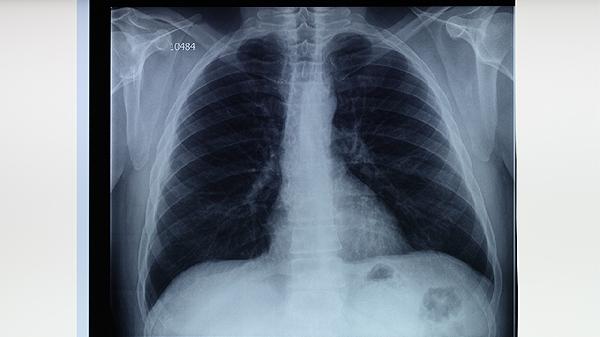

肺结核患者需在医生指导下规范治疗,家庭治疗的核心是配合医疗方案并做好隔离防护。肺结核的治疗方法主要有规范用药、环境消毒、营养支持、症状监测、心理疏导等。

肺结核患者家庭治疗期间应保持规律作息,每日进行散步等轻度活动但避免剧烈运动。注意气候变化及时增减衣物,预防呼吸道感染。治疗满2个月、5个月和疗程结束时需复查胸部CT评估疗效,所有家庭成员都应进行结核菌素试验筛查。患者痰菌转阴前须严格实施呼吸道隔离,康复后仍需定期随访2年监测复发可能。